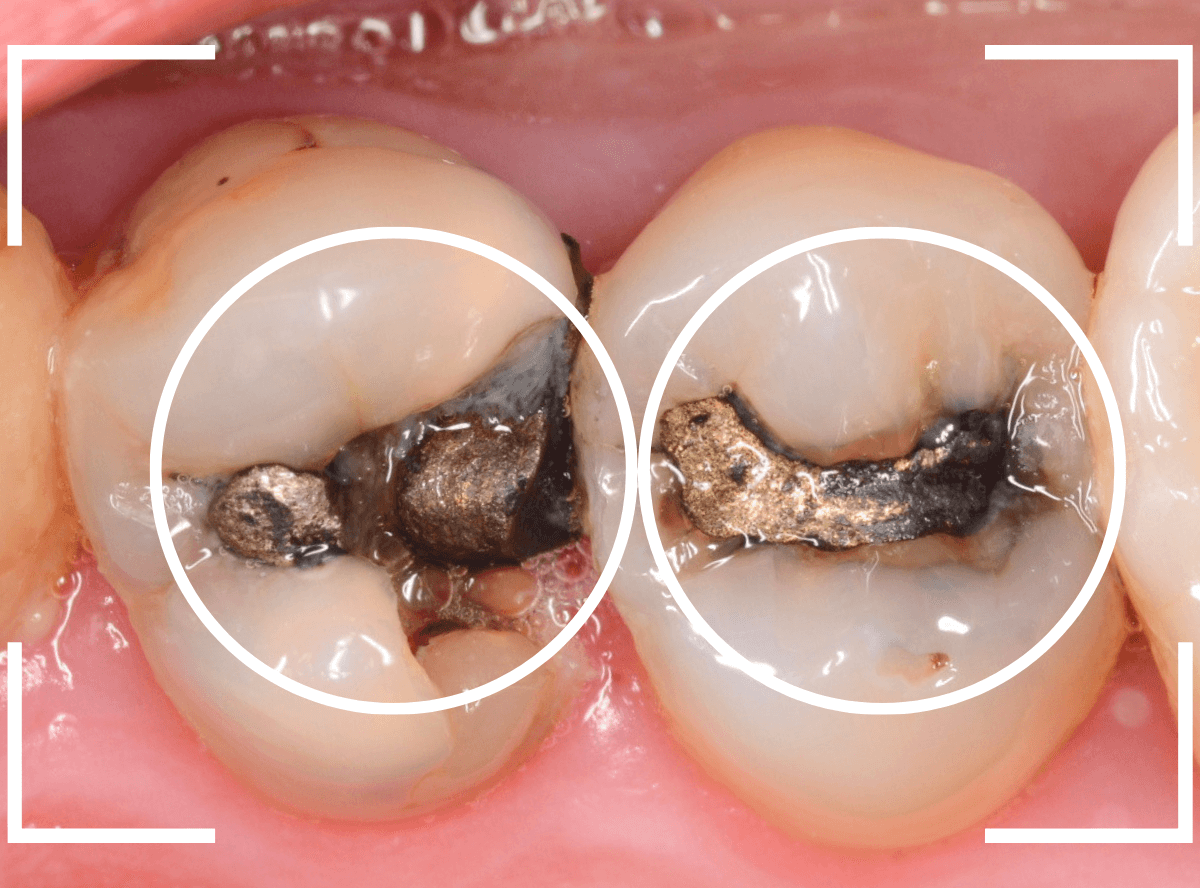

Case.9 金属の下で深い虫歯

レントゲン写真で金属のつめものの中の虫歯が見つかった方です。

つめものの中の虫歯の厄介なところは、自覚症状がない事も多い事です。

さて、外から見た感じでは、私が見ても中で虫歯進行してるかわかりません。

症状がなくても、定期メンテナンスとレントゲン写真を使った確認が有用です。

虫歯の治療を開始してつめものを外したところです。

左側の歯は、つめものの下のお薬の中で落とし穴のように虫歯になっていました。

右側の歯の赤く染まっている部分も虫歯です。

左側の歯のお薬を全部除去しました。

全ての虫歯を除去しました。

かなり中で広がっていた虫歯でした。

虫歯は見た目や症状からだけで判断できません。